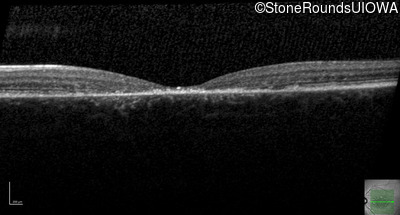

Optical Coherence Tomography - Right - 20/160 +2

Exemplar / OCT Stack